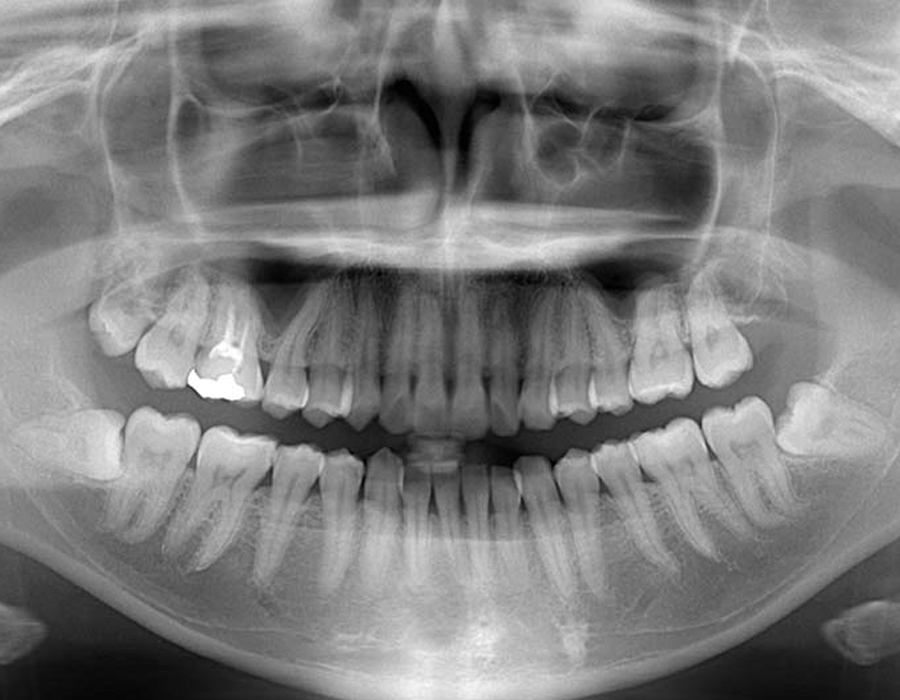

短時間で安全に親知らずを抜歯するためには、事前の画像検査が欠かせません。CT撮影により、親知らずや顎の骨の状態を詳しく知ることができます。その上でお口の中を拝見します。現状と歯科医としての意見をお伝えし、患者様と話し合いながら、抜歯を行うのか、残して経過観察に留めるか決定します。